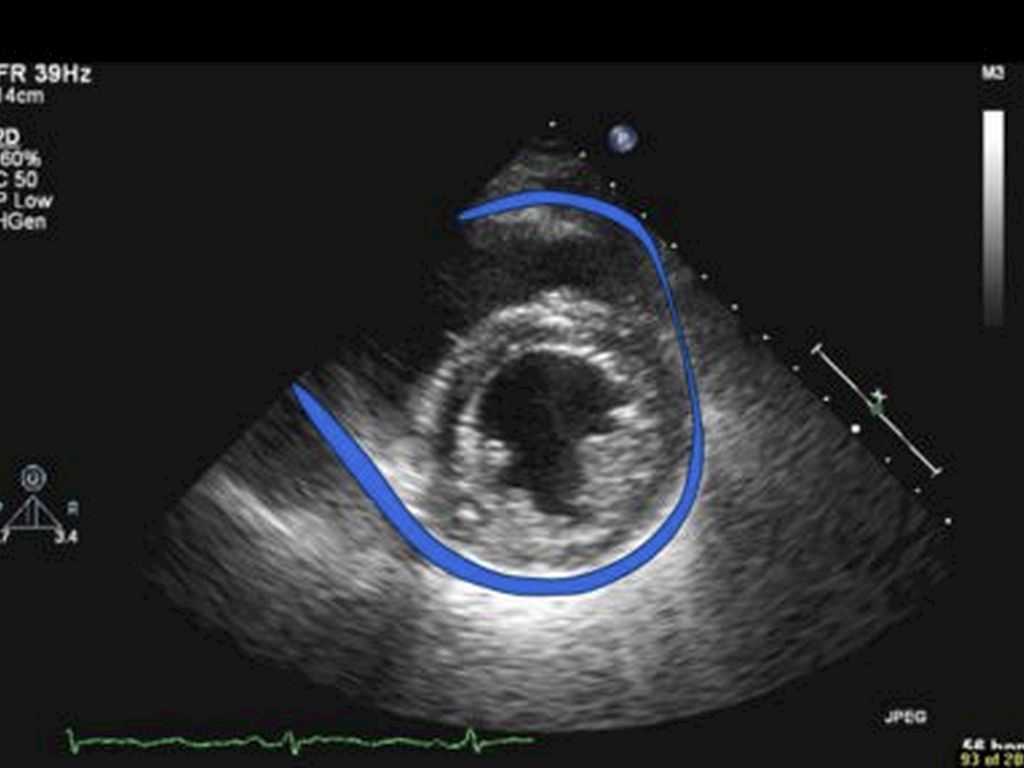

Pericardial Effusion is an abnormal amount of fluid between the heart and the pericardium, which is the sac surrounding the heart. Pericardial effusions are associated with many different medical conditions. Most pericardial effusions are not harmful, but large pericardial effusions can cause problems by impairing heart functions.